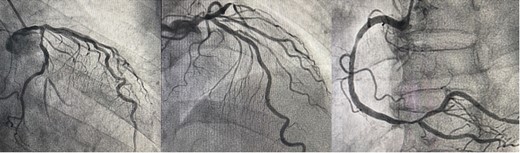

The patient was a 75-year-old man with a non-ST elevation myocardial infarction. His underlying diseases were hypertension, dyslipidemia, and chronicle smoking. Coronary angiography revealed triple coronary artery disease with left main trunk (Fig. 1). His transthoracic echocardiography showed no valvular disease, normal left ventricular (LV) ejection fraction (EF) of 64% and left ventricular enlargement (LV end-diastolic diameter [LVDd]; 6.8 cm). In conclusion, He was referred for MICSOPCAB.

This coronary angiography indicates triple-vessel coronary artery disease. (LMT: 50% stenosis, LAD proximal: 90% stenosis, OM2: 80% stenosis, RCA distal: 90% stenosis)